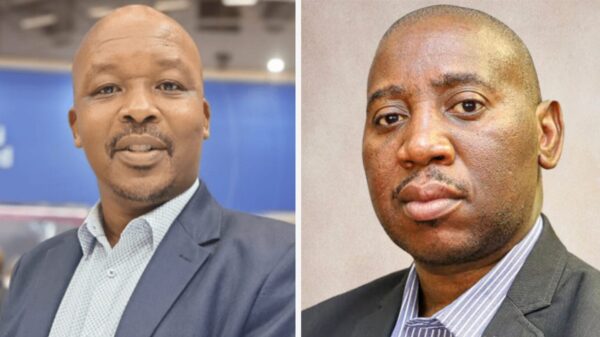

Colin Xu, an assistant professor in the Department of Psychology and Communication within the College of Letters, Arts, and Social Sciences, will spearhead the development of machine learning models intended to improve the early detection of adverse health outcomes affecting military servicemembers and their families. “These projects will examine how machine learning techniques can be applied to psychiatric and public health data in order to strengthen military health,” Xu noted. “Through these machine learning models, we hope to improve early identification and prediction of PTSD risk for servicemembers and enhance prediction and prevention of adverse health outcomes for servicemember families.”

The first award, a $4.2 million collaborative DoD-funded initiative, allocates $974,000 to U of I and will focus on integrating smart wearable devices, biochemical markers, and biophysical signals to advance PTSD screening and diagnosis. This collaborative effort involves co-principal investigators from various institutions, including Manish Bhomia from the Uniformed Services University, Dr. Christina La Croix from Walter Reed National Military Medical Center, Sameer Sonkusale from Tufts University, Dr. Steven Cohen from Northwestern University, and CJ Brush from Auburn University. Xu’s team will create machine learning models to harness biomarker and biophysical data collected from wearable technologies, enhancing the diagnostic accuracy for PTSD.

The second grant, totaling $1.9 million, with $361,000 designated for U of I research, will concentrate on understanding how deployment-related stress impacts military families, potentially leading to harmful behaviors. Xu’s team will collaborate with co-principal investigators Elizabeth Hisle-Gorman, Christin Ogle, and Dr. Stephen Cozza from the Uniformed Services University to identify predictors of family violence, substance misuse, suicidality, and injury within military families.